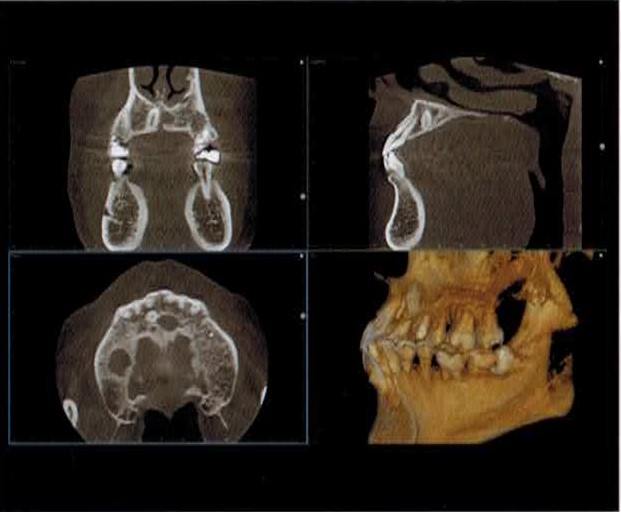

歯科用CT

歯科用CTを導入しました!

CTとは、コンピュータ断層撮影(Computed Tomography)の略でエックス線とコンピュータ処理を利用し、画像の再構築を行うことで、断層写真を得られる装置のことです。

その中でも、歯科用CTは歯科に特化したCT装置のことです。従来のレントゲン(パノラマ・デンタル)は平面的だったのに対し、歯科用CTでは立体的(3D)に診断することができます。

CTと聞くと、大きな機械に寝転がり、撮影するイメージがあると思います

しかし、歯科用CTは座ったまま撮影ができ、撮影時間も約10秒程と短く、医科用CTに比べ、被曝量も少ないため、患者様への負担を大幅に軽減できます。

歯科用CTでの撮影